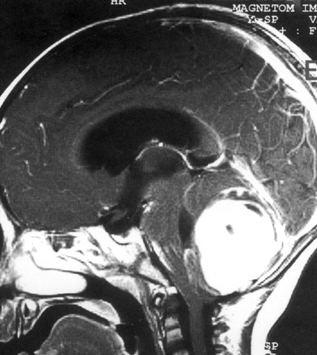

问题 病历摘要:??患儿男性,11岁。半年前开始出现行走不稳,常无故跌倒。半月前出现发作性剧烈头痛,伴恶心呕吐。体检:T36℃,P100次/分,R22次/分,BP100/60mmHg,神清,言语较缓慢,双眼外展约不及边,双眼侧视时有小幅度水平眼震。四肢肌力正常,右上肢肌张力较低,坐位姿势不稳,常不自主摇晃,双上肢指鼻不准,行走蹒跚步态,足距扩大,身前倾。 下一步应首先采取哪些措施?提示:多次缝合伤口,仍有脑脊液渗漏。